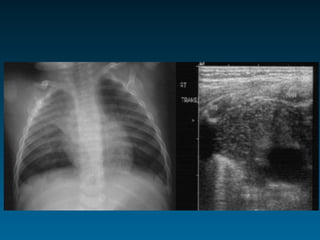

14 μηνών, Εμπύρετο προ 2μήνου, παθολογική α/α

θώρακος, επανέλεγχος